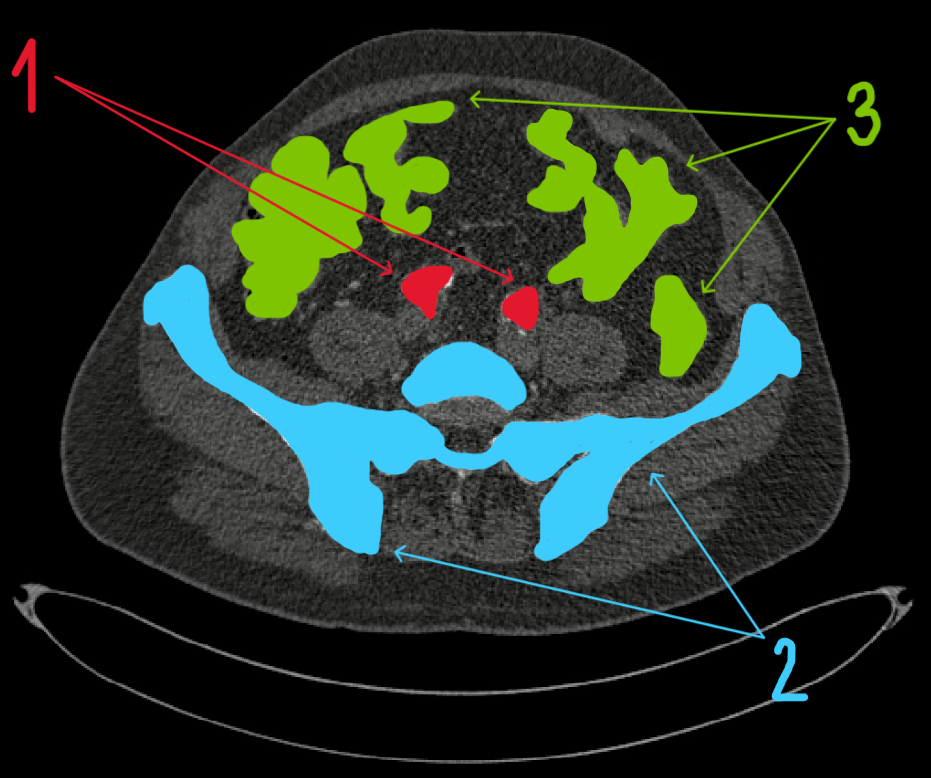

Dolní oblast dutiny břišní (z videa)

- kyčelní tepny

- kost pánevní

- střeva